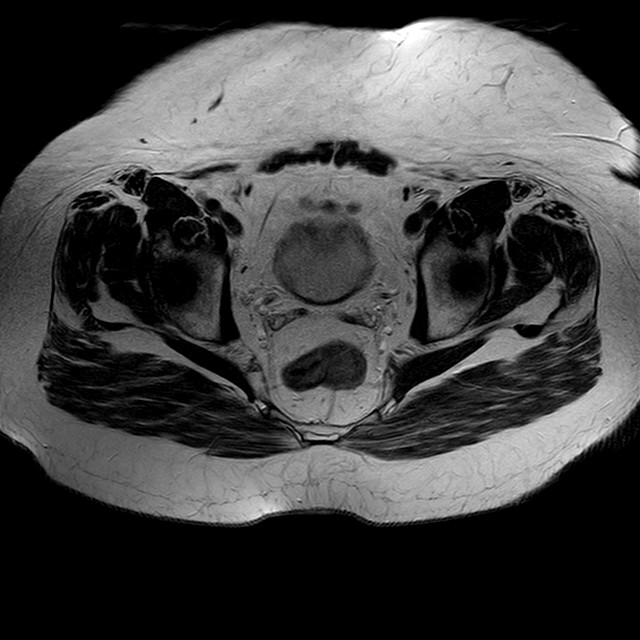

Esami: RMN BACINO

eT2w TSE

Evidenti e simmetriche alterazioni osteofitosiche in regione coxo femorale con riduzione delle rime articolari. Degenerazione completa del cercine glenoideo. Non attuali segni di versamento articolare. Non segni di edema osseo che escludono attuale algodistrofia od osteonecrosi. Lieve e simmetrica riduzione del trofismo della muscolatura glutea.